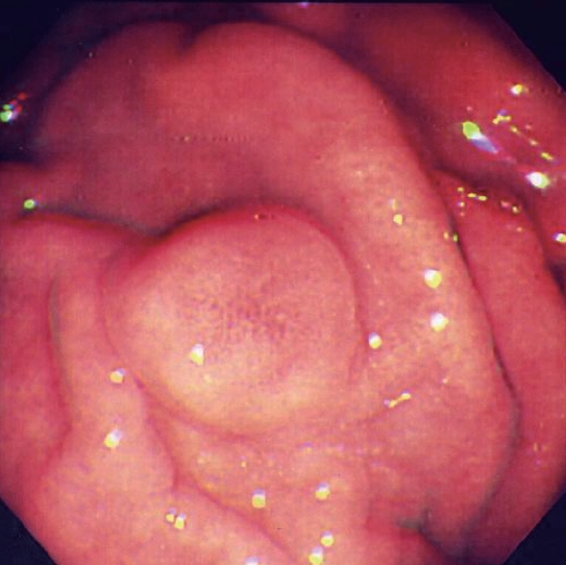

Endoscopic view of multiple gastric stromal tumors after suctioning of hemorrhagic products (Courtesy Dr. V. Penopoulos)